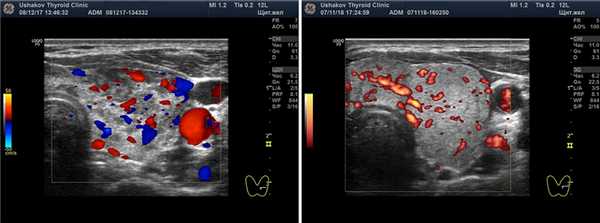

Рисунок 4. УЗИ ― допплеровское исследование интенсивности кровотока щитовидной железы. Показаны несколько вариантов: Ослабленный кровоток, нормальный кровоток, Малое усиление кровотока, Умеренное усиление кровотока и Значительное усиление кровотока.

Рисунок. 6. Интенсивность кровотока узлов щитовидной железы. Показаны несколько вариантов интенсивности кровотока: Малой интенсивности, Умеренной интенсивности, Значительной интенсивности.